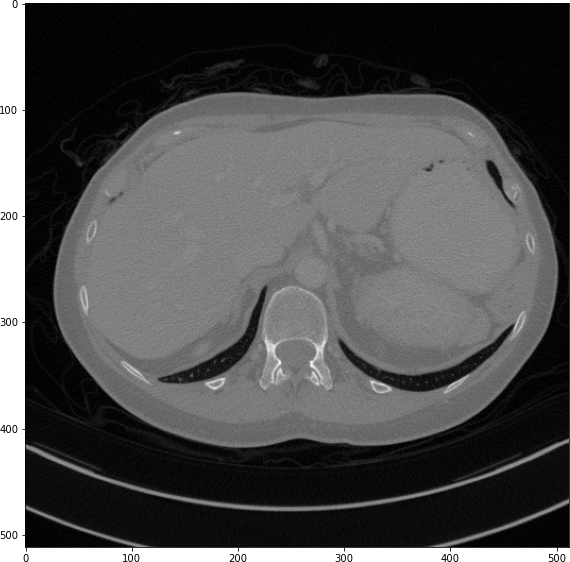

The results from all conducted experiments, represented as mean ±plus-or-minus\pm standard deviation, are tabulated in this section. We assessed the performance of our proposed simulation method against Simple Averaging, Gaussian Averaging, and Direct Downsampling. This was accomplished by simulating images with a thickness of 3mm from those with a thickness of 1mm, utilizing the 2016 Low Dose CT Grand Challenge dataset. The results outlined in Table III provide a comparative analysis of different thick-slice simulation methods used in two datasets from the 2016 Low Dose CT Grand Challenge. Both the PSNR and the RMSE were used as key performance indicators for these methods. The data clearly demonstrate that the proposed method significantly outperformed Simple Averaging, Gaussian Averaging, and Direct Downsampling in both datasets (D45 and B30). The highest PSNR values were obtained with the proposed method, yielding 49.7369 ±plus-or-minus\pm 2.5223 and 48.5801 ±plus-or-minus\pm 7.3271 for D45 and B30 datasets, respectively. The proposed method also registered the lowest RMSE with values of 0.0068 ±plus-or-minus\pm 0.0020 and 0.0108 ±plus-or-minus\pm 0.0099 for D45 and B30, respectively. These results indicate a superior level of accuracy and reliability in the proposed method. The statistically significant differences were confirmed by a Wilcoxon signed-rank test with p-value ¡ 0.05, implying that the improvements from the proposed method were not due to random chance. These findings support our first hypothesis that the proposed simulation method provides a more efficient and precise approach to thick-slice simulations compared to traditional methods. To provide a more comprehensive evaluation, visual comparisons from axial, coronal and sagittal plane were also undertaken, as depicted in Figures 2 to 4. In summary, Our proposed method demonstrated substantial enhancements in terms of both PSNR and RMSE, indicating a distribution more closely aligned with the authentic thick-slice image.

Figure 2: Axial-plane thick-slice image quality comparison across four simulation methods.

Refer to caption

(a) True Thick-slice image

(b) Simple Averaging

RMSE: 0.0250, PSNR: 38.0530

(c) Gaussian Averaging

RMSE: 0.1758, PSNR: 21.1182

(d) Direct Downsampling

RMSE: 0.0348, PSNR: 35.1697

(e) Proposed Simulation

RMSE: 0.0051, PSNR: 51.8504

Figure 3: Coronal-plane thick-slice image quality comparison across four simulation methods.